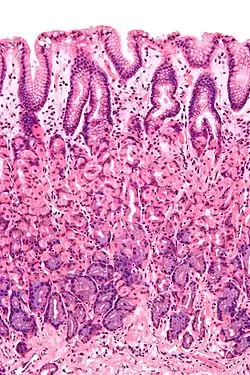

The stomach wall, with simple columnar epithelium visible as a lining at the top.

Simple columnar epithelium is a single layer of columnar epithelial cells which are tall and slender with oval-shaped nuclei located in the basal region, attached to the basement membrane. In humans, simple columnar epithelium lines most organs of the digestive tract including the stomach, and intestines. Simple columnar epithelium also lines the uterus.

The shape of the simple columnar epithelium cells are tall and narrow giving a column like appearance. the apical surfaces of the tissue face the lumen of organs while the basal side faces the basement membrane.[1] The nuclei are located closer along the basal side of the cell.[1]

Absorptive columnar epithelium is characterized as having a striated border on its apical side, this border is made up of non-motile microvilli allowing for increase surface area for absorption.[1] These are known as non-ciliated columnar epithelium. Non-ciliated simple columnar epithelium is made up of glandular goblet cells which secrete mucin to form mucus.[1] The rest of the cell is made up of cytoplasm with membrane bound secretory granules which secrete the mucin, and are found towards the apical surface of the cell.[1]